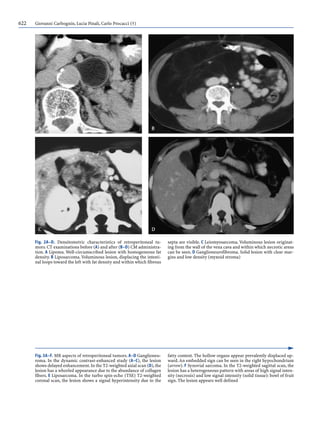

Fig. 3A–F. MR aspects of retroperitoneal tumors. A–D Ganglioneu-

roma. In the dynamic contrast-enhanced study (A–C), the lesion

shows delayed enhancement.In the T2-weighted axial scan (D),the

lesion has a whorled appearance due to the abundance of collagen

fibers. E Liposarcoma. In the turbo spin-echo (TSE) T2-weighted

coronal scan, the lesion shows a signal hyperintensity due to the

fatty content. The hollow organs appear prevalently displaced up-

ward.An embedded sign can be seen in the right hypochondrium

(arrow). F Synovial sarcoma. In the T2-weighted sagittal scan, the

lesion has a heterogeneous pattern with areas of high signal inten-

sity (necrosis) and low signal intensity (solid tissue): bowl of fruit

sign. The lesion appears well defined